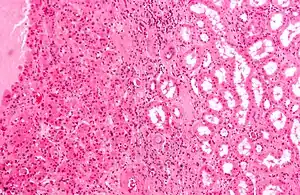

| Micrograph of a renal oncocytoma, a type of benign kidney tumour. H&E stain. | |